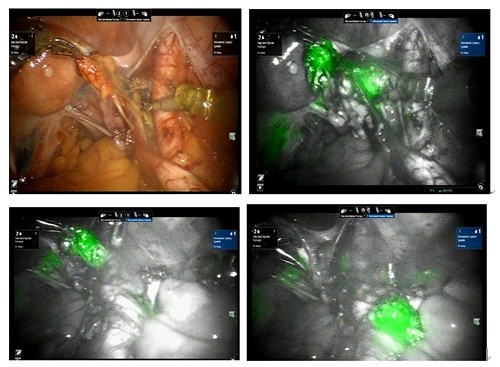

左圖:龐醫師說明子宮內膜癌。

右圖:達文西螢光影像系統就是透過螢光標註細胞組織,讓醫師能準確切除需要切除的組織。

現代的達文西螢光影像系統能讓手術醫師精準地切除需要切除的淋巴結。所謂的螢光就是靛氰綠indocyanine green (ICG) 在近紅外光(near infrared,NIR)照射下會發出綠色的螢光。由於近紅外光具有穿透人體組織的特性,可以激發人體內的靛氰綠發出螢光。靛氰綠最早是在二次世界大戰期間發展成為相片顯影的試劑,1957年開始在醫學上使用,目前廣泛應用在心血管造影與肝功能檢查等。近年來也運用於子宮內膜癌和子宮頸癌手術中,配合特殊的影像系統讓骨盆的前哨淋巴結在術中顯示,讓手術醫師能精準地切除需要切除的淋巴結。